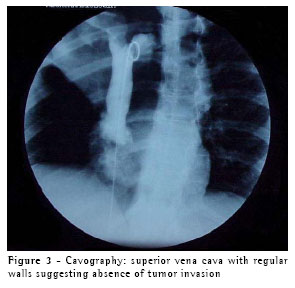

upper lobe (caused by occlusion of the upper lobe bronchus) that extended up to the juxtacarinal portion of the main bronchus, accompanied by infiltration of the wall of the main left bronchus, which resulted in invasion of the right branch of the pulmonary artery and of the arch of the azygos vein. There was no sign of invasion of the chest wall or of pleural effusion (Figure 2). Tomographic findings led us to suspect invasion of the superior vena cava and azygos vein. Therefore, we performed a cavography, which did not reveal any involvement of these structures (Figure 3).